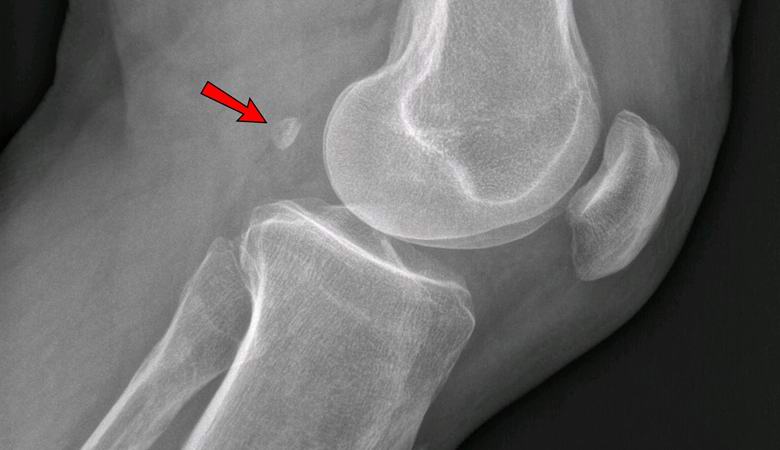

Pokud v roce 1918 mělo jen 11% pozemšťanů v jednom z nich fabella noha, dnes je přítomna u 39% lidí. Tento sezamový tvar kost roste v tloušťce šlach za kolenem a anatomicky se podobá mikroskopické patelle.

Lékaři stále nedokážou zjistit, proč tento základ se vrací do lidského těla a proč je to nutné. První lékaři si mysleli, že Fabella je jen neškodný, zbytečný orgán, odborníci však nyní dospěli k závěru, že její přítomnost v koleni může způsobit osteoartrózu. Byli tam dokonce i lékaři kdo doporučil každému, kdo má fabella, aby ji odstranil chirurgicky tak, aby ve stáří netrpěl deformací osteoartritida.

Dnes každá biologická učebnice naznačuje, že lidská kostra sestává z 206 kostí. V budoucnu však možná taková data uznáno za zastaralé a budou hovořit o 206-208 kostech, protože mnoho lidí už má jednu nebo obě bajky. Tohle kost, kterou mnozí lékaři považují, lze nazvat dodatkem kostra, “protože to je nejen k ničemu, ale může také sloužit způsobit zdravotní potíže. V kontaktu s kolenní chrupavkou, vede k těžké osteoartróze.